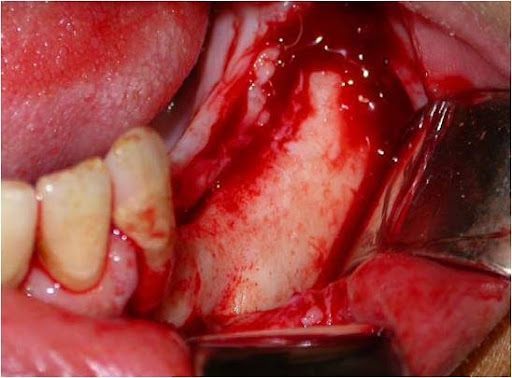

A incisão deve ser linear sobre a crista alveolar, iniciada no trígono retromolar e, com pequeno desvio para lingual, segue em direção à região do canino, sendo acompanhada de uma extensão no rebordo alveolar vestibular anterior ao canino, como forma de garantir um retalho que irá cobrir todo o defeito ósseo, protegendo-o de fenestrações ou de infecções. Uma vez descolado o retalho localiza-se o forame mentoniano e libera-se com extremo cuidado o periósteo do feixe no nervo mentoniano (Fig. 4).

Fig. 4 - Após a incisão o retalho totalmente afastado, mostrando o forame mentoniano já perfeitamente liberado do periósteo.